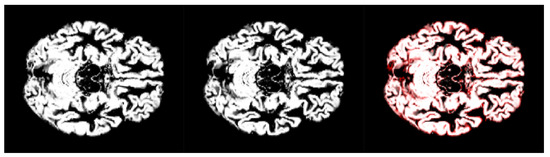

- We have introduced the notion of significant pixels, i.e., the pixels of the MRI images where the white (resp. gray) matter decays in the considered two-year time span, significantly differ between and subjects. The number of significant pixels, in the brain slices where the phenomenon mostly appeared, according to the different values obtained after performing a permutation test on all the pixels of the images, i.e., , , and , was about 4%, 2%, and 1.5% of the totality of the white matter and slightly more, i.e., 6%, 4%, and 2.5%, of the totality of the gray matter. Such a small number of significant pixels is sufficient to discriminate between and , as reported in Table 2 and Table 3, using the K-means clustering technique. Not surprisingly, when considering the white matter, all the and subjects were correctly clustered, i.e., the white matter decay of subjects significantly differed from that of ones. On the other hand, when considering gray matter, the subjects were correctly classified, while 6 of the 40 subjects were assigned to the class, with a percentage of error of 15%. This can be ascribed to the fact that Alzheimer’s disease strongly impacts on the white matter first, and later leads to the decay of the gray matter.We also underline that, according to the wide and consolidated literature, the most involved areas of the brain affected by Alzheimer’s decay are the medial portion of the temporal lobe, where the hippocampus, amygdala, entoryl cortex, and parahippocampal cortex reside. These areas are located inside the selected slice intervals where most of the significant pixels were detected. As an example, Figure 7 shows the significant pixels of slice 58, where a peak in the white and gray matter occurred, with the involved brain areas highlighted.

- Moving to the -to- predictive capability of the K-means model restricted to significant pixels, again we found different percentages according to the considered white or gray matter in the considered two-year time span. As expected, analyzing the white matter a high percentage of , namely, (Table 2), showed an pattern-like decay, similar to what was detected in [16,17,18] on the same dataset. So, our result, with a time span of two years, was slightly below the results presented in [20], where after one year only 8 of 37 patients with converted to (22%), verifying the reduction in the regional glucose metabolic rate, a truthful signal of early-onset .This high percentage of pattern in could be attributed to the similarly located decay of white matter in the two classes of subjects, as reported in [43]. This study involved 23 , 15 , and 15 subjects that underwent diffusion tensor magnetic resonance imaging (DTI), an advanced MRI technique extremely sensitive to white matter alterations. The authors found that patients with had an increase in mean diffusivity in the limbic, interhemispheric, cortico-cortical, and corticospinal tracts and, similarly, patients with showed an increase in axial diffusivity only in tracts projecting to the frontal cortex and splenium of the corpus callosum.On the other hand, time passing caused a milder effect on the gray matter of subjects, whose analysis revealed only 29% of -to- cases (see Table 3),, in accordance with the more optimistic studies in the work of [8], obtained through using machine learning techniques on fMRI images.Table 2 and Table 3 report the obtained statistics on the classification performance of subjects, together with the related indexes. In Figure 6, the distributions of subjects’ distances within the clusters show smaller distances between the subjects and the related centroids when white matter is considered with respect to gray matter. This implies that the classification using white matter produces tighter clusters and, consequently, a stronger accuracy than gray matter. All the clusters show some borderline subjects that produce small local maxima while moving away from the centroids. However, the computation of the Dunn indexes showed the high reliability of the obtained clustering. Again, we underline that the small diameter of the cluster may also be due to the smaller variability in the age range of the subjects. However, this does not constitute an issue in the final results of the research.